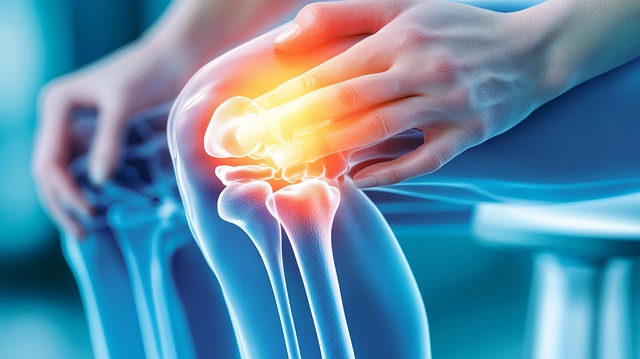

5. 고관절 통증 완화 셀프 관리

- 하루 10~15분 스트레칭

- 무리한 하체 운동 중단

- 얼음찜질(염증기), 온찜질(근육 긴장)

- 엉덩이·코어 강화 운동

- 낮은 소파, 양반다리, 다리 꼬기 피하기

- 걸음걸이 교정

특히 엉덩이 근육이 약하면 고관절에 직접 부하가 걸려 고관절 통증 증상이 악화될 수 있어, 대둔근·중둔근 강화는 꼭 필요한 부분입니다.